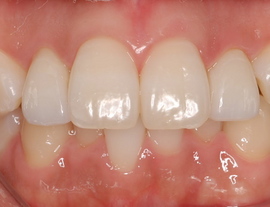

SET後

ラミネートベニアはもちろんセラミック。

e-MAXです。かなり強度があります。

接着はリンクマスターで接着。

1番のポイントは患者さんとよく話合い、ファイナルの形をどうしたいか、だと思います。